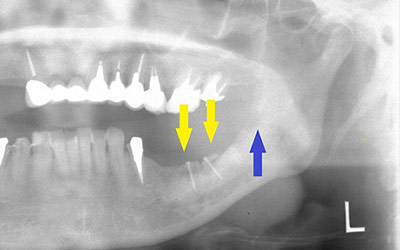

インプラントを埋入するためには、骨を増やさなければならず、患者様ご自身の骨を移植する、自家骨移植術を行なうこととしました。写真、青色の矢印で示す、智歯周辺の骨を採取し、黄色の矢印の部位に骨片を移植、チタン製の小さなスクリューで骨片を固定するという手術を行いました。細く、白く映っているのが骨を固定したミニスクリューです。